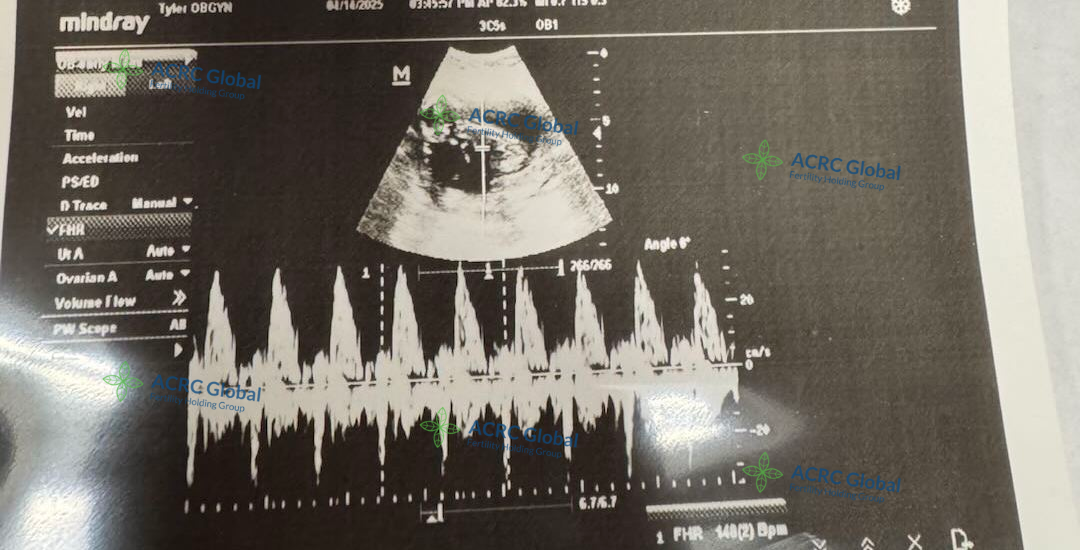

自移植以来,爱妈一直非常配合,不仅定期更新近况,还主动分享每次产检照片,让准妈妈远在国内也能放心。用药、打疫苗、日常调养,她都认真对待,事事细心,沟通顺畅,让整个孕期进展得非常顺利。大家都满怀期待,希望这个小生命能在她的温柔守护下,健康成长,顺利到来!